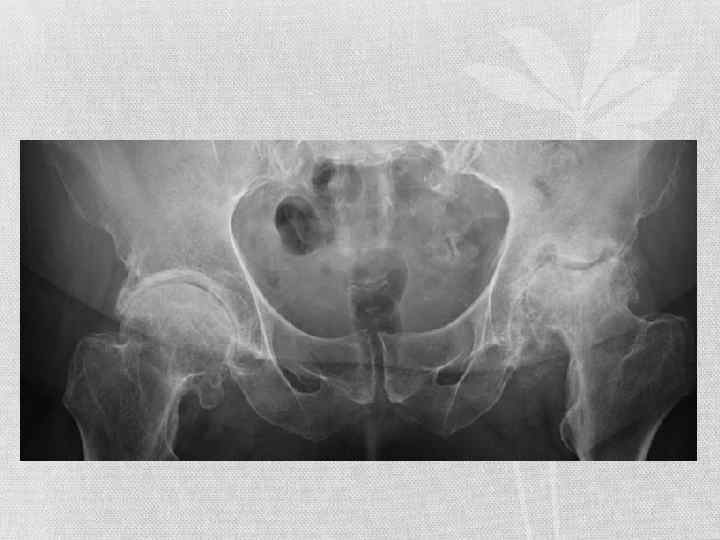

Коксартроз 2 -й степени сопровождается сильными болевыми ощущениями, которые зачастую носят хронический характер, и пациент вынужден принимать обезболивающие. Контрактура не позволяет человеку ходить на дальние расстояния, а позднее приковывает к постели инвалидному креслу. Нередко больные жалуются на крепитацию (скрипящие или хрустящие звуки в суставе). Нога со стороны поражённого ТБС зрительно укорачивается по причине перекоса таза. На рентгеновском снимке явно видна деформация бедренной головки. • Коксартроз 3 -й степени выражается в полном смыкании краёв суставной щели, приводящем к абсолютной контрактуре. Пациент испытывает болевые ощущения не только при нагрузке на сочленение, но и без неё. На данной стадии наблюдается сильная крепитация. По всему суставу образуются склеротические участки.